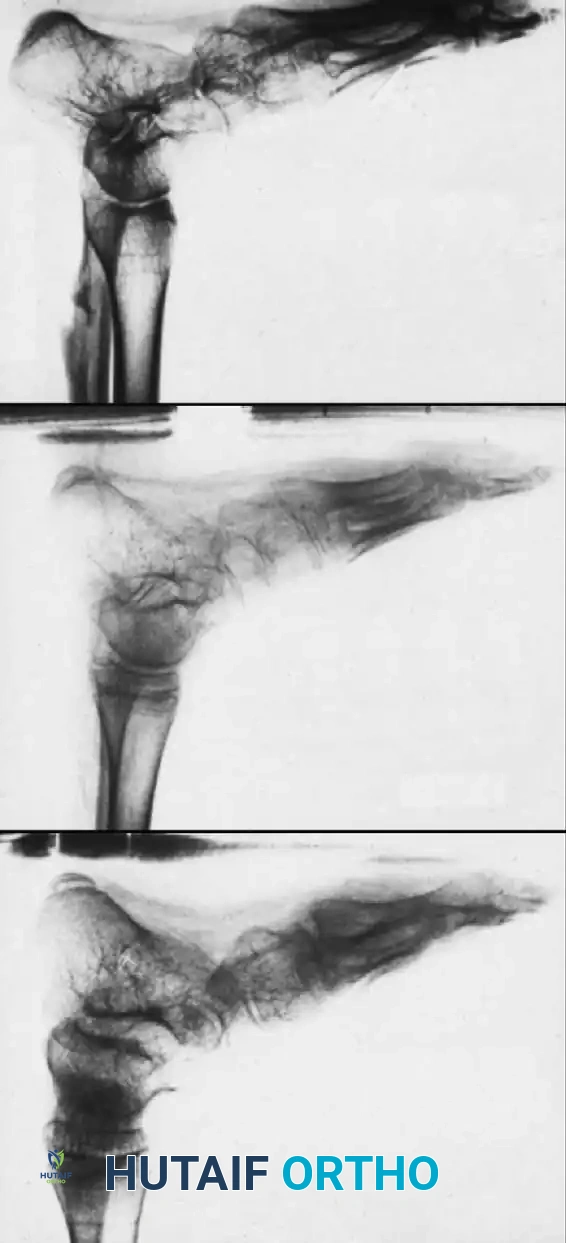

Arthrodesis of the Foot:

In adults or older adolescents with fixed, static deformities, tendon transfers alone are insufficient. The Triple Arthrodesis (fusion of the subtalar, calcaneocuboid, and talonavicular joints) is the definitive procedure for stabilizing a flail hindfoot and midfoot.

Image

Surgical Warning: In growing children, bony procedures should be delayed until skeletal maturity (typically >12 years of age) to prevent severe growth arrest and secondary deformities. Extra-articular subtalar arthrodesis (Grice-Green procedure) can be utilized in younger children to stabilize the hindfoot without violating the physes.